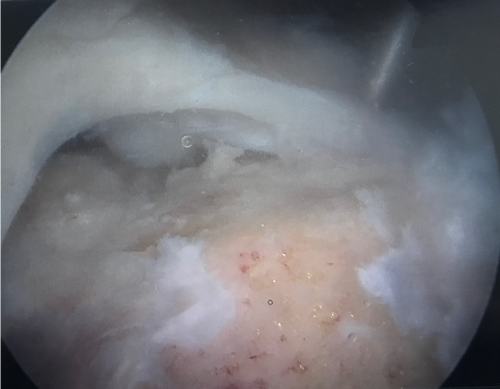

Treatment depends on the age and demand of the patient, size and reparability of the tendon and symptoms such as pain and stiffness. Small tears with a lot of pain can be treated with anti-inflammatory steroid injection and rest followed by physiotherapy. Large tears in particular those associated with significant weakness or tears that have failed to respond to non-surgical management over an appropriate length of time may be repaired typically by arthroscopic (keyhole) surgery or rarely by open methods. In older patients with massive and often longstanding rotator cuff tears the best treatment may be to replace the shoulder with a reverse geometry total shoulder replacement.